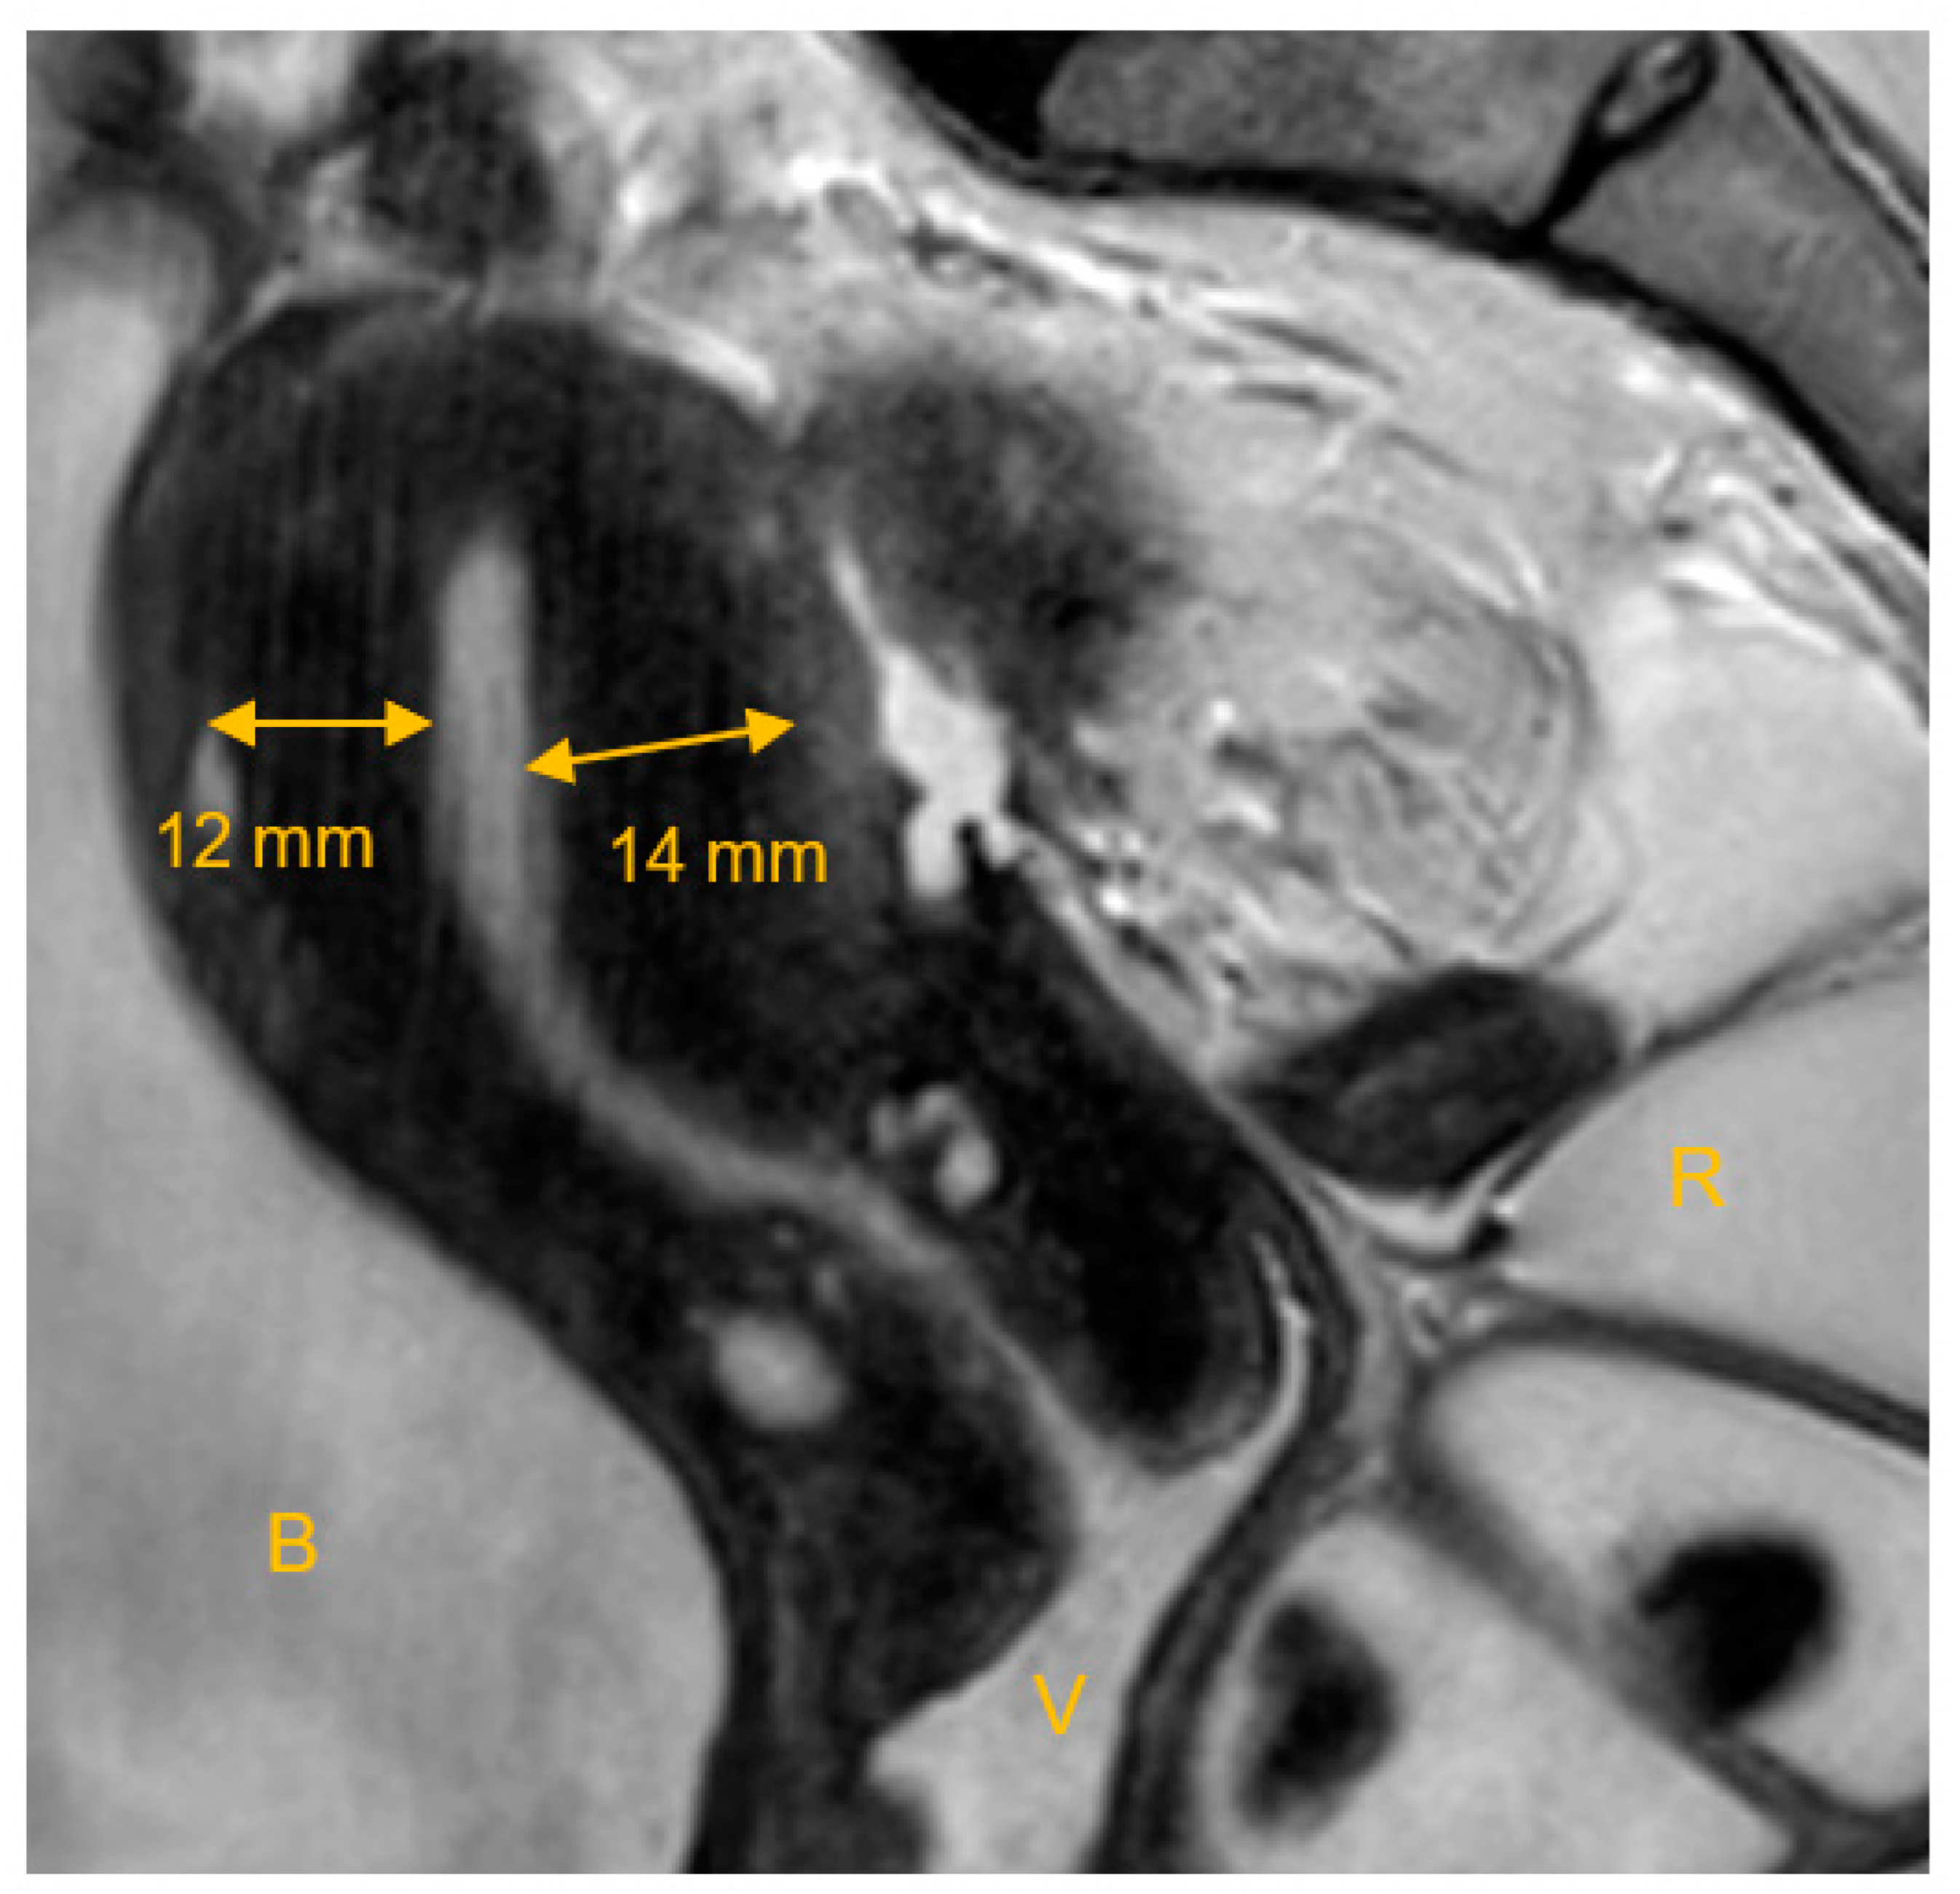

The junctional zone (JZ) is of crucial importance in the evaluation of adenomyosis and its impact on fertility. In 1983, Hricak et al. first described the functional uterine zone, which is the junction between the endometrium and the inner myometrium [38]. There are three layers that can be distinguished on T2-weighted images: (1) an area of high signal intensity corresponding to the endometrial stripe; (2) an inner area of low signal intensity close to the basal endometrium, the JZ or the subendometrial layer; and (3) an outer region of moderate signal intensity, which is the subserosal zone or the outer myometrium [35,39]. Figure 2 shows MRI characteristics of the JZ.

Figure 2.

MRI characteristics of the uterine junctional zone. T2-weighted MRI in the sagittal plane, showing the widened junctional zone marked with arrows. B: bladder, V: vagina filled with ultrasound gel, R: rectum filled with ultrasound gel. Image acquisition on 3T, Ingenia Philips Healthcare, with a T2 TSE sequence.

Both MRI and TVS appear to be equally capable of making the diagnosis of adenomyosis, but MRI seems to be superior to TVS in identifying adenomyosis. It has equal sensitivity but a higher specificity than TVS (sensitivity: MRI 0.70 (0.46–0.87), TVS 0.68 (0.44–0.86) (p = 0.66); specificity: MRI 0.86 (0.76–0.93), TVS 0.65 (0.50–0.77) (p = 0.03)) [29,35]. Measurement of the JZ serves a further diagnostic tool. Adenomyosis may be considered likely when the thickness of the JZ exceeds 12 mm, although there is no clear definable JZ on MRI in around 20% of premenopausal women [36]. Adenomyosis can also be suspected when the thickness of the JZ is between 8 mm and 12 mm or in the presence of other specific signs, such as a relative thickening of the JZ in a localized area, a poor definition of the JZ margins, or high-signal foci on T2- or T1-weighted sequences [23,35].